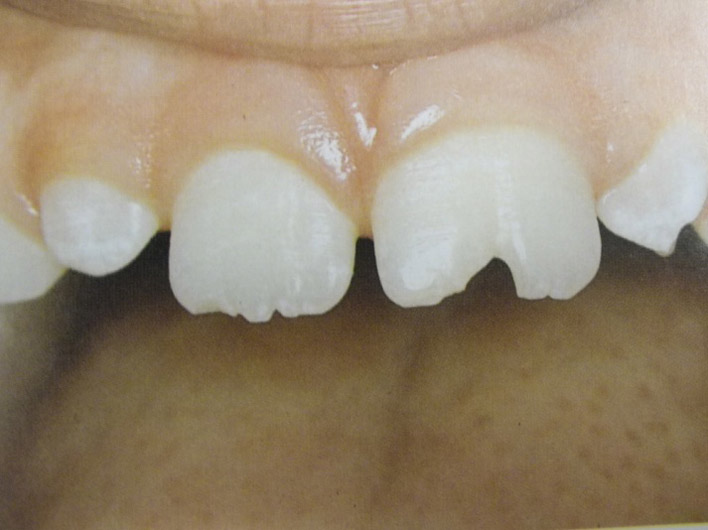

Τερηδόνα βρεφικής και νηπιακής ηλικίας ή τερηδόνα θηλασμού

Η τερηδόνα βρεφικής και νηπιακής ηλικίας εμφανίζεται σε μικρά παιδιά ηλικίας 2 έως 5 ετών, τα οποία έχουν τερηδονισμένα ένα ή και περισσότερα νεογιλά δόντια. Η τερηδόνα αυτής της μορφής οφείλεται σε λάθος τρόπο διατροφής του παιδιού και μπορεί να εξελιχθεί γρήγορα και σε μεγάλη έκταση επηρεάζοντας το σύνολο το δοντιών που βρίσκονται στο στόμα.

Η κυριότερη αιτία εμφάνισης της τερηδόνας αυτής της μορφής είναι το τάισμα με το μπιμπερό ενώ το παιδί κοιμάται. Κατά τη διάρκεια του ύπνου η ποσότητα του σάλιου μειώνεται και το γάλα, ανεξάρτητα αν περιέχει ή όχι ζάχαρη, παραμένει πάνω στα δόντια και προκαλεί τερηδόνα. Ακόμη και το μητρικό γάλα μπορεί να έχει τις ίδιες συνέπειες, εφόσον το παιδί θηλάζει κατά βούληση κατά τη διάρκεια της νύχτας.